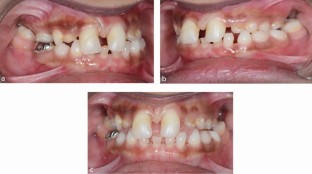

Primary molar teeth that are retained beyond their exfoliation pose a clinical decision-making challenge for dental teams. The retention of these teeth may be due to absence of a permanent successor. As a result, careful planning is required to determine if retention or extraction is necessary. This article aims to discuss the prevalence of retained primary molars, assessment and treatment planning considerations, from both orthodontic and restorative perspectives.

Explains considerations for extraction of primary molars and consequences if retained, such as infraocclusion.